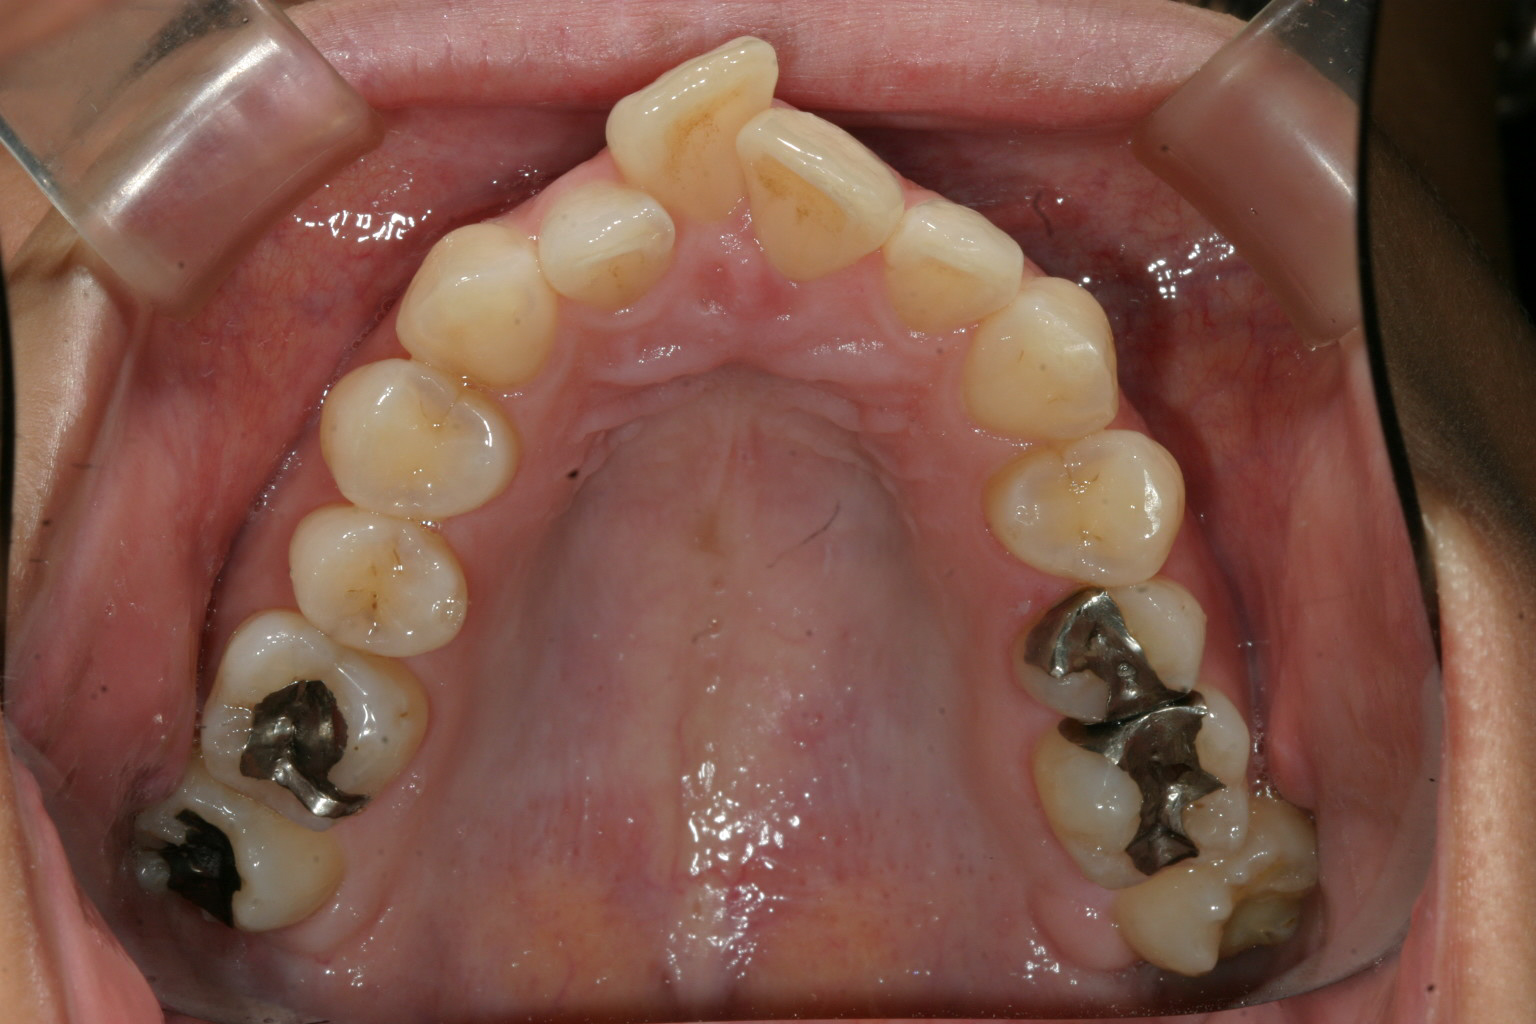

完全に歯列が尖っています。 両側犬歯の幅が狭い為にアーチがV字型になっています。

下顎もかなりの叢生です。